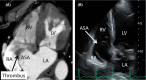

We experienced a very rare case of surgical management of a giant atrial septal aneurysm. It is an interesting case and is supported by preoperative, intraoperative, and pathology images.